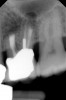

Clinical procedure: If apical bone loss is present (Figure 1) a collagen/gelatin sponge (eg, Gelfoam®, Pfizer Inc., www.pfizer.com) can be placed apically so that the MTA can be delivered to the desired working length. (Any other surgical resorbable sponge would also work, such as OraPlug® [Salvin Dental Specialties, www.salvin.com], Surgifoam® [Midwest Dental, www.mwdental.com], or Surgispon® [Aegis Lifesciences, www.surgispon.com]). This is done by taking a small piece (2 mm x 2 mm) of the resorbable sponge and pushing it down to and through the root apex with an endodontic file. Once this is done, MTA is packed down the canal with a custom-fitted cone. The clinician can use a rubber stopper on the gutta-percha cone to know the exact length of MTA placed in the apical third (Figure 2). Once the apical third is sealed with 3 mm to 5 mm of MTA, the remaining coronal canal space can be back-filled using a warm gutta-percha technique (Figure 3).

Fig 2. MTA placed in the apical third.

Figure 2